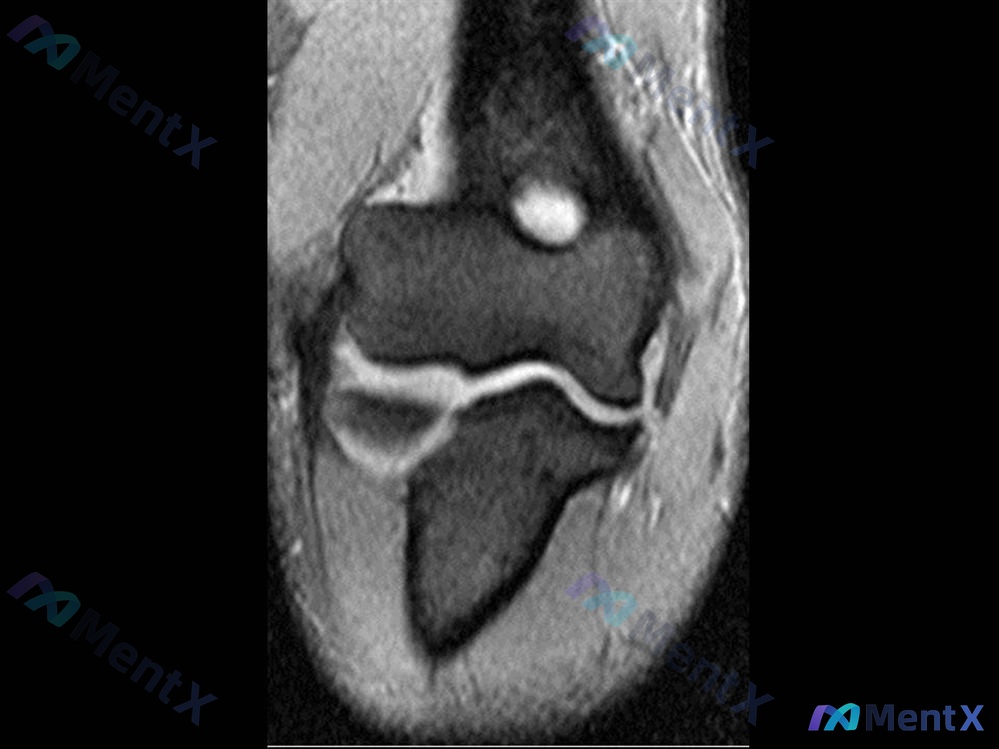

影像学检查(MRI 冠状位 T2):

- 关节腔内可见明显积液信号。

- 肱骨远端与尺骨/桡骨关节间隙上方可见一枚圆形/椭圆形明显高信号结节(疑似游离体或软骨成分)。

- 骨皮质轮廓尚完整,未见明显骨折线。

- 内侧副韧带(MCL)形态连续性尚可,未见明显断裂信号。